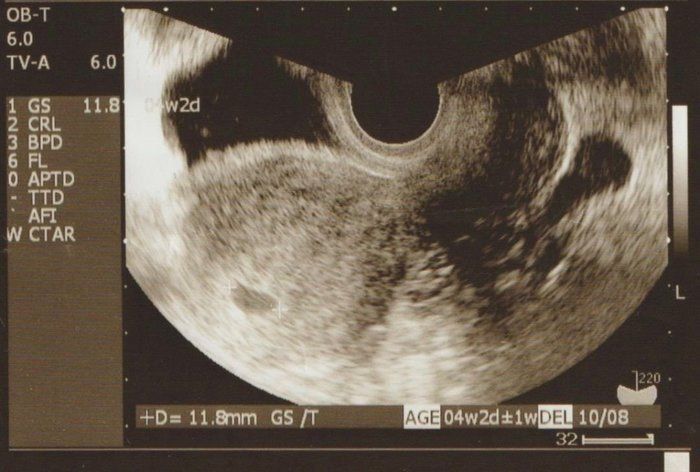

妊娠5週目のおなかの赤ちゃんはどう見える? みんなのエコー写真・超音波写真

ママライターのみなさんの妊娠出産体験談から、妊娠5週の赤ちゃんのエコー写真を紹介します。

チャーミー小結さんの妊娠5週目のエコー写真

妊娠検査薬で陽性反応が出た翌日、病院を受診して最初に撮ったエコー写真です。この時点で妊娠5週目。初めて見る画像でしたが、モニターに映った瞬間「いる!」と胎芽の入っている胎嚢(袋)が確認できました。